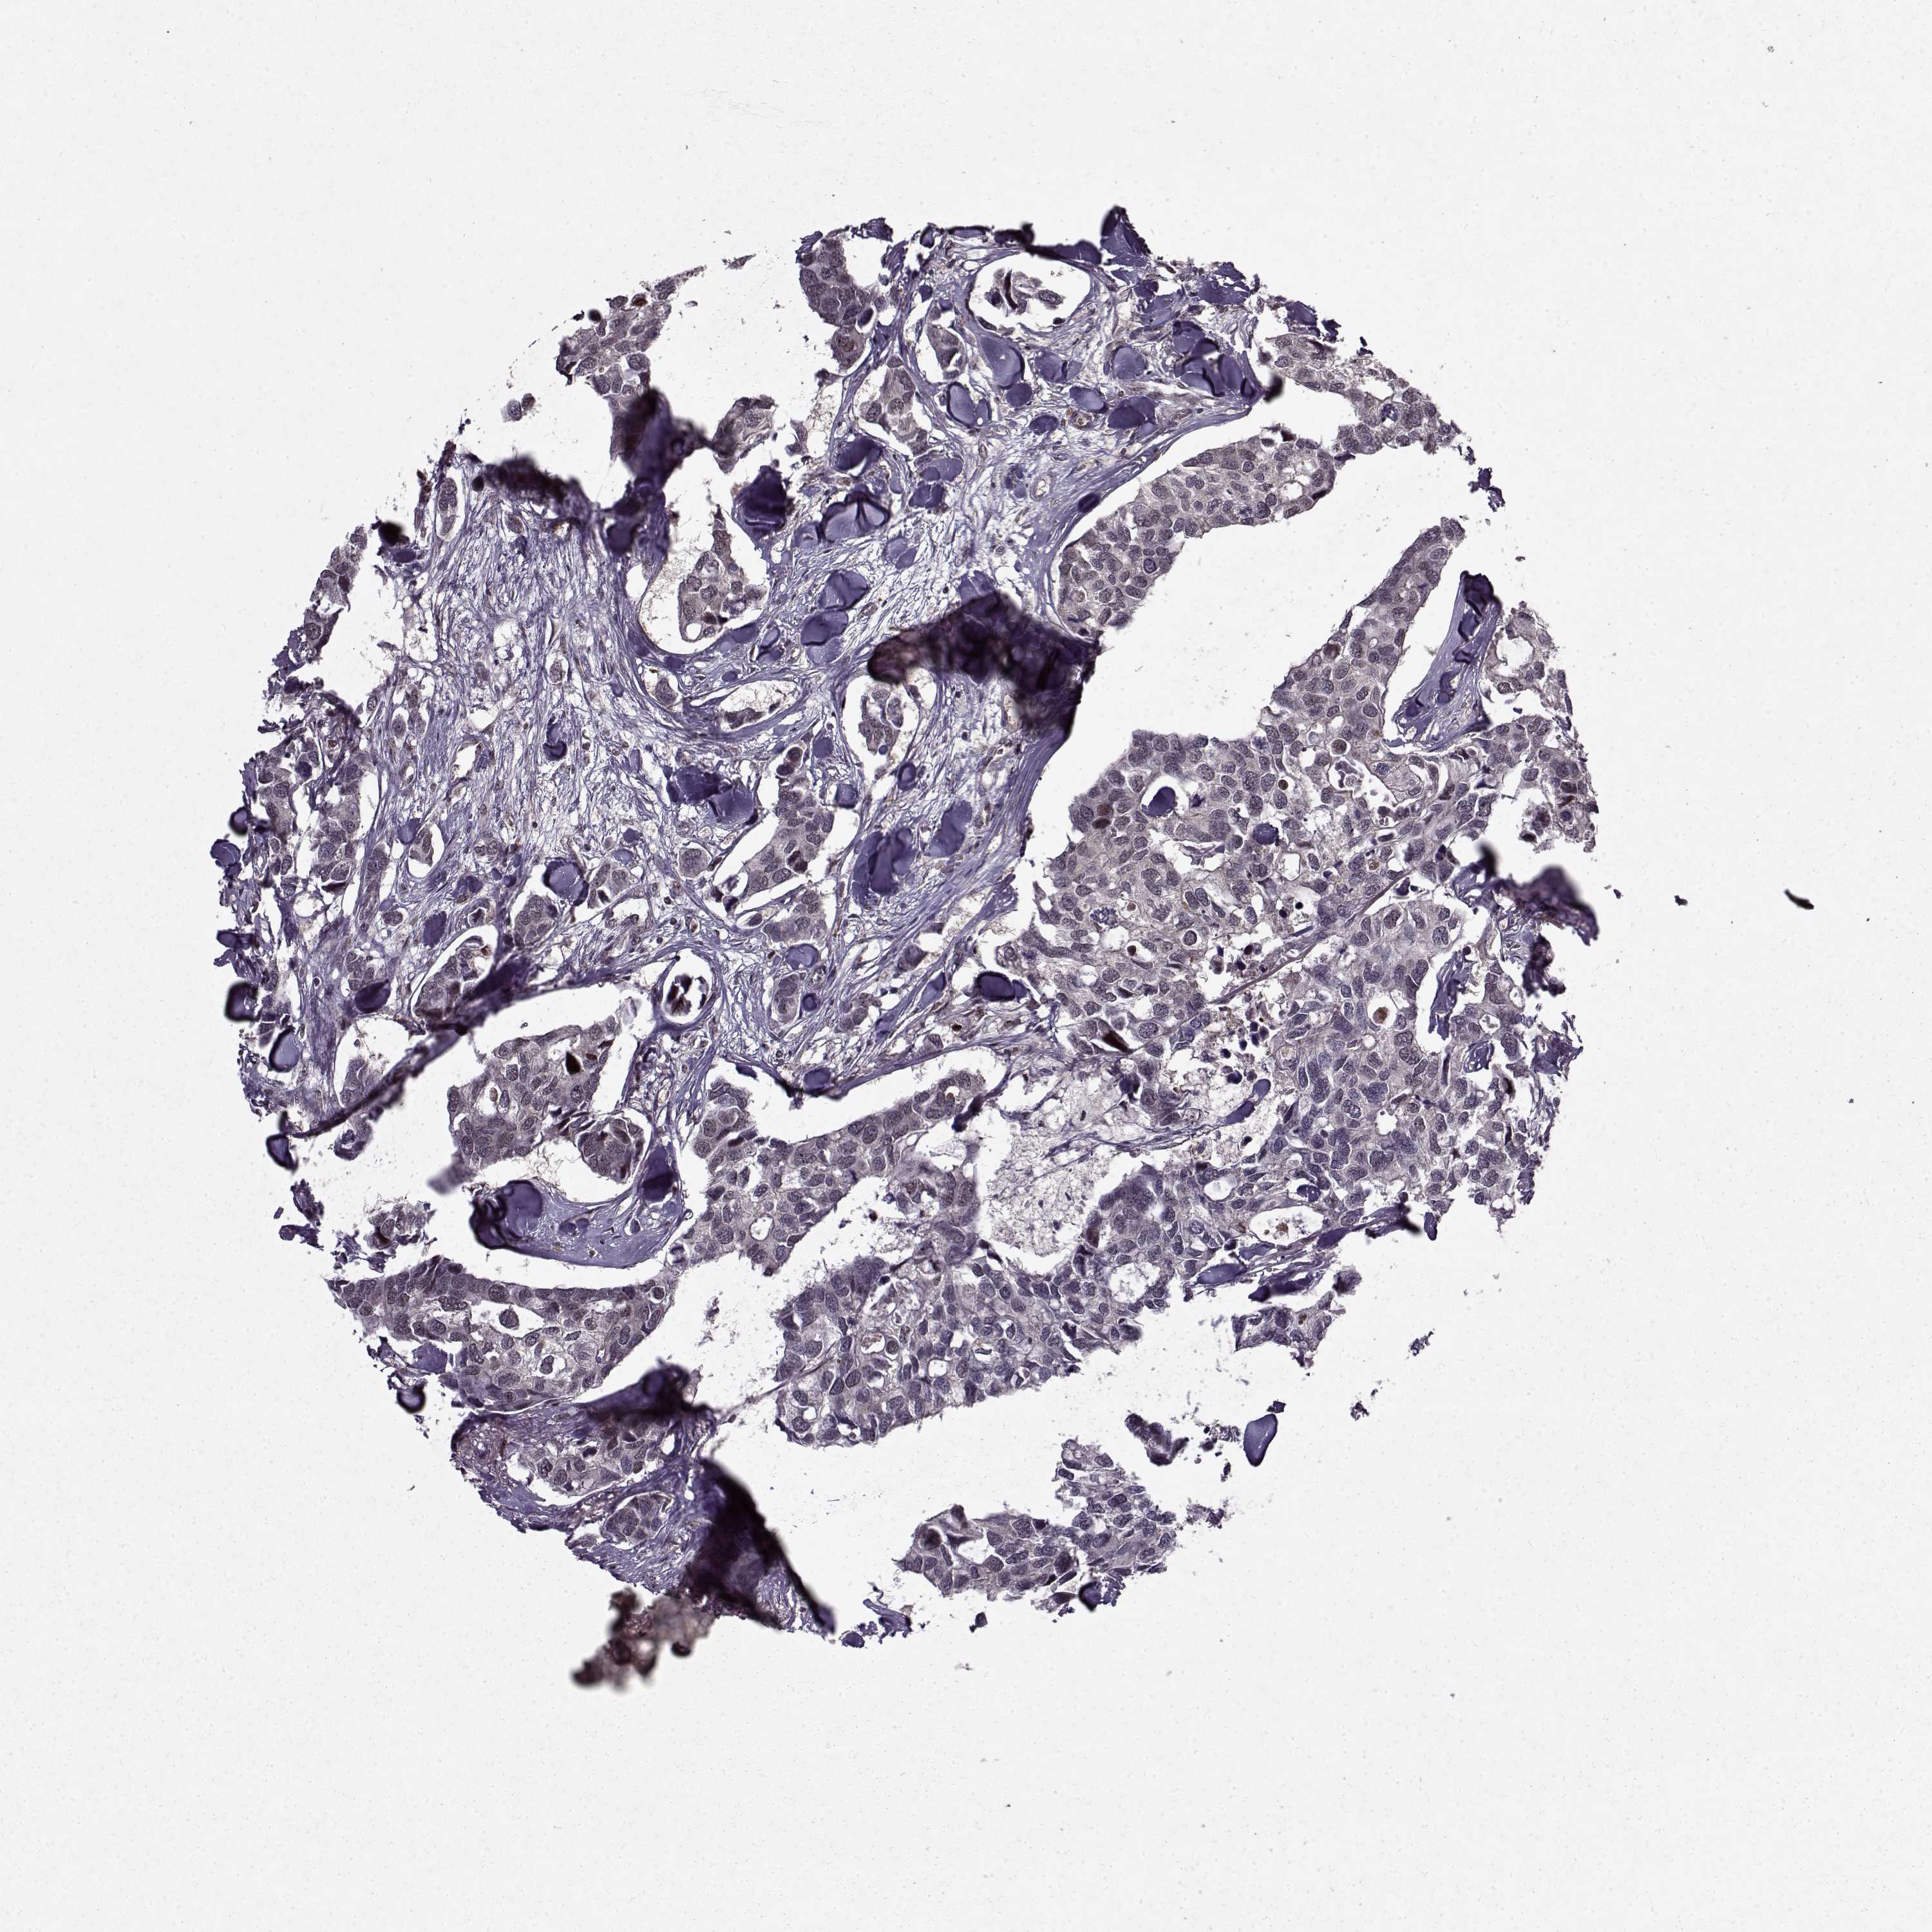

BRCA TCGA BRCA VALIDATION PROTEIN EXPRESSION

ANTIBODIES

AND

VALIDATION